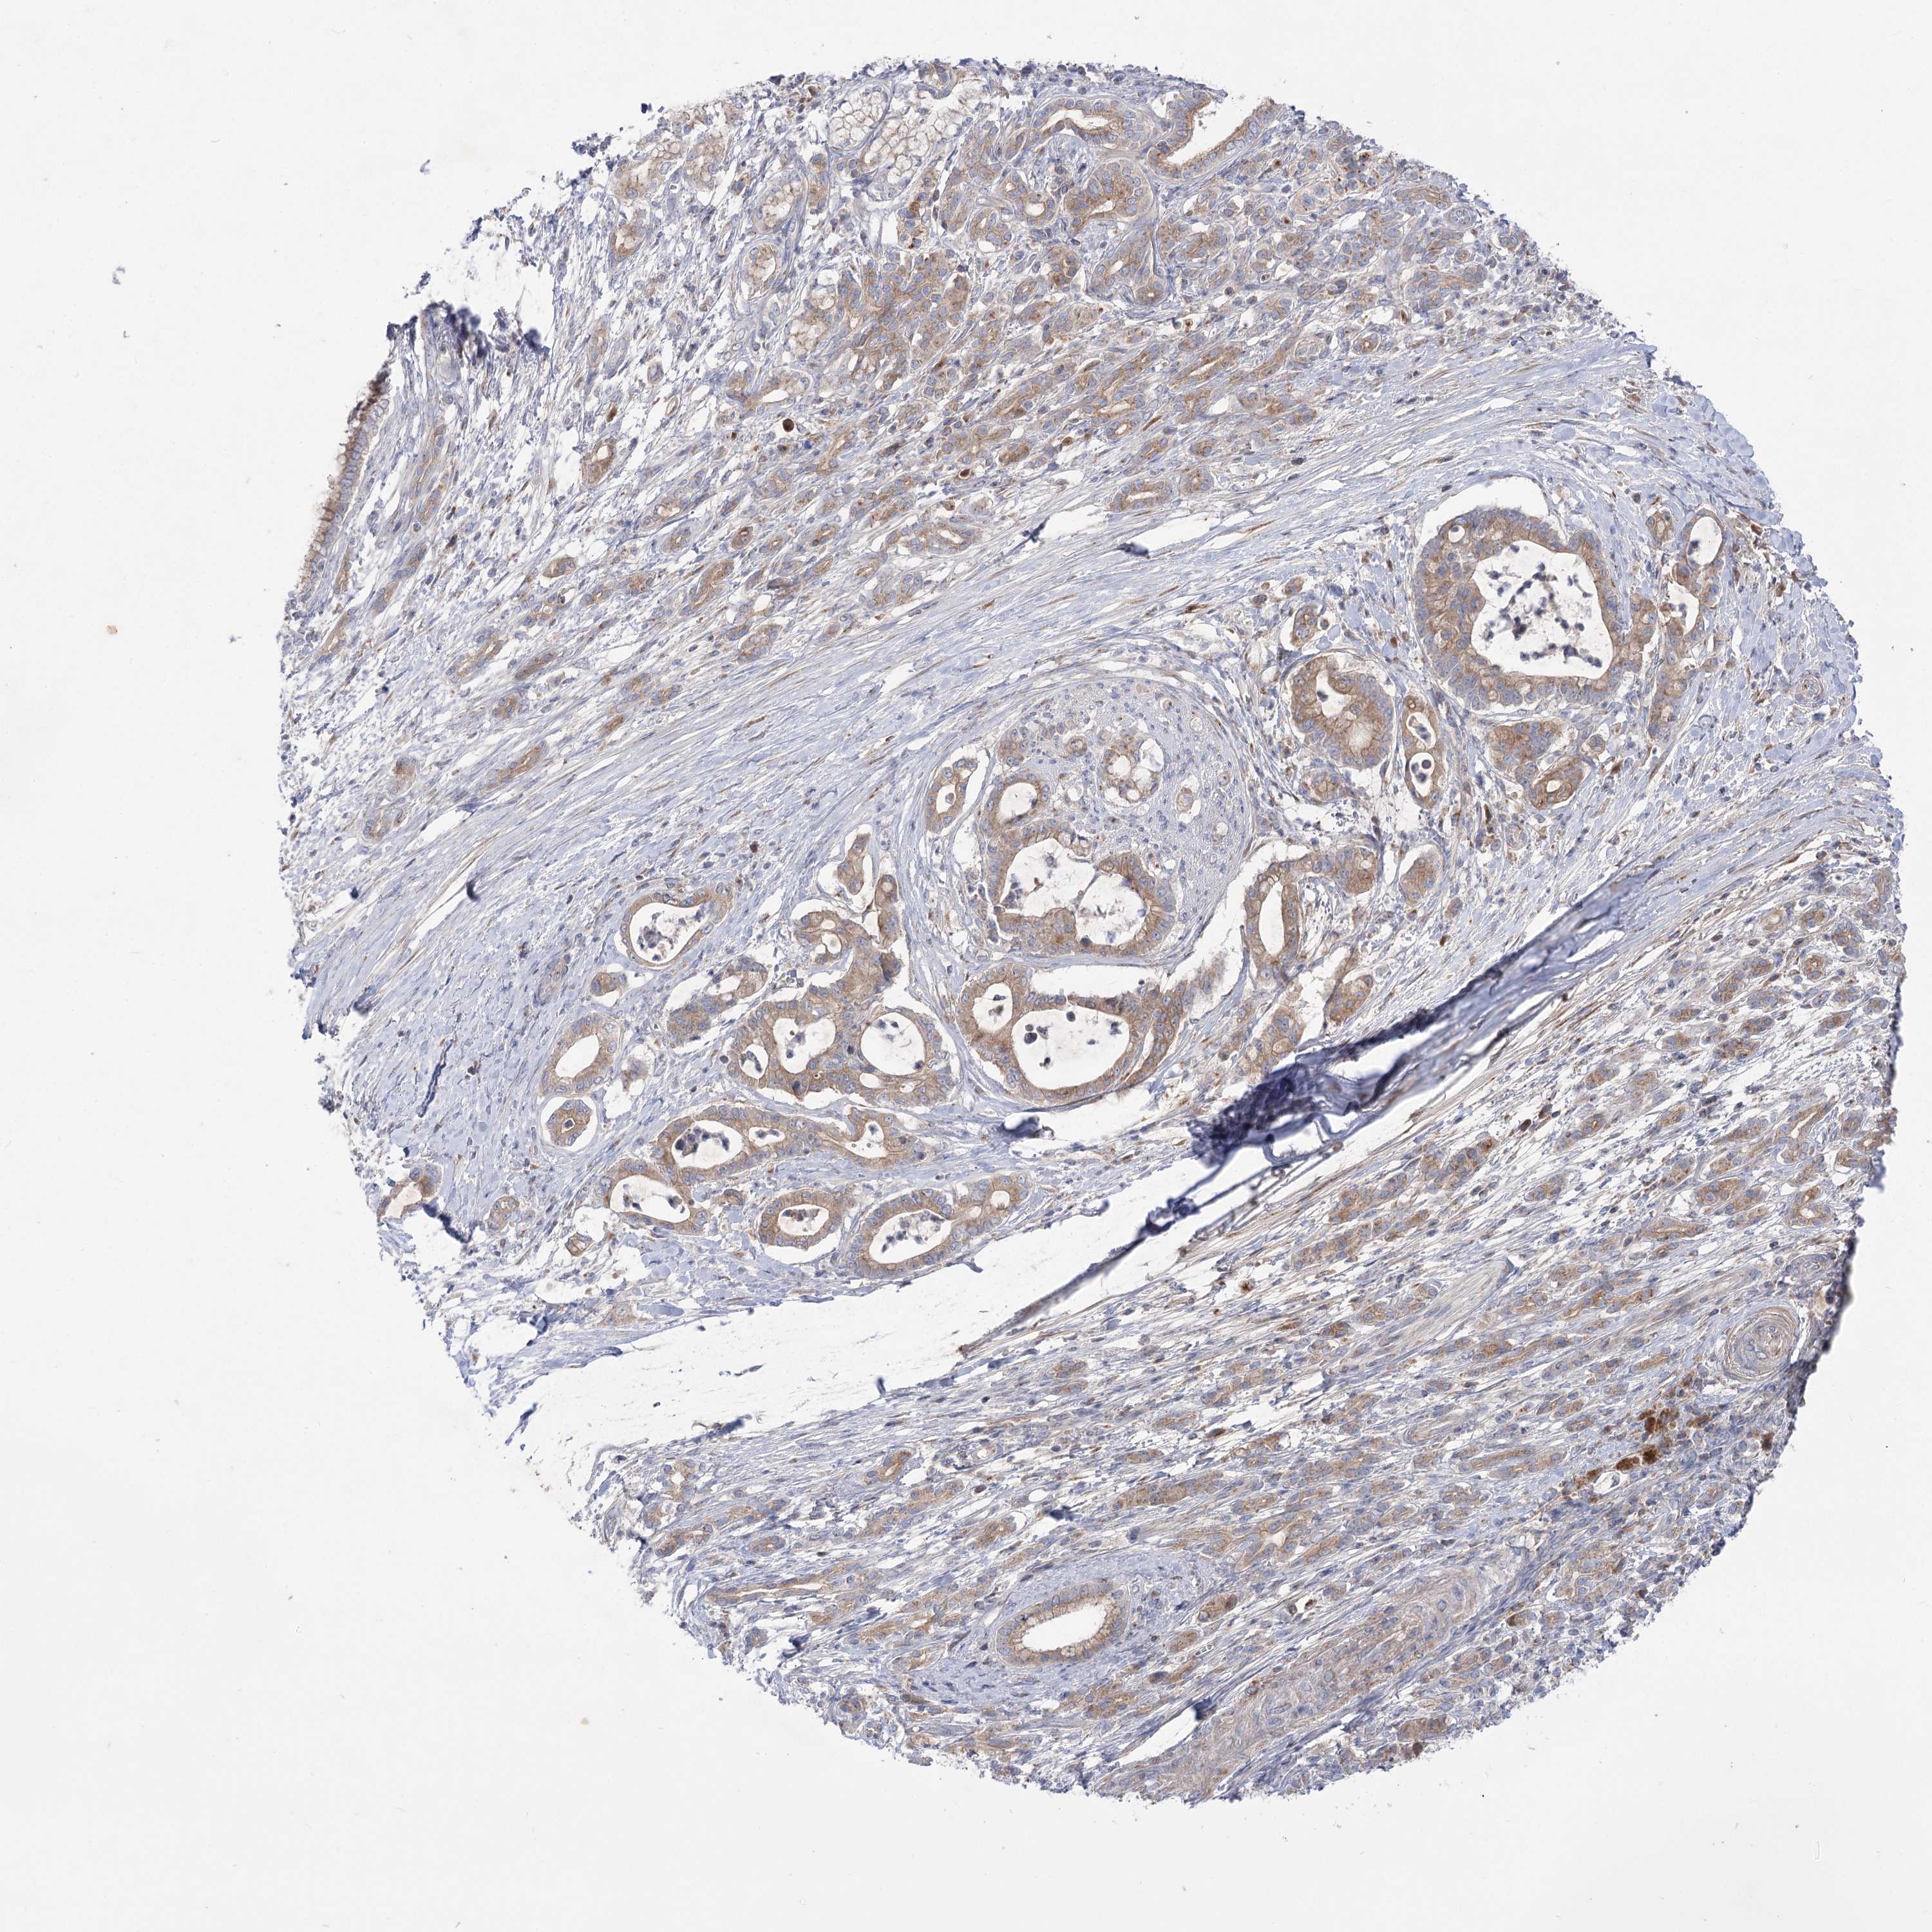

PANCREATIC CANCER - Protein expressioni

A mouse-over function shows sample information and annotation data. Click on an image to view it in a full screen mode. Samples can be filtered based on level of antibody staining by selecting one or several of the following categories: high, medium, low and not detected. The assay and annotation is described here.

Note that samples used for immunohistochemistry by the Human Protein Atlas do not correspond to samples in the TCGA dataset.

Antibody stainingi

Antibody staining in the annotated cell types in the current human tissue is reported as not detected, low, medium, or high, based on conventional immunohistochemistry profiling in selected tissues. This score is based on the combination of the staining intensity and fraction of stained cells.

Each image is clickable and will lead to virtual microscopy that enables deeper exploration of all samples and also displays staining intensity scores, fraction scores and subcellular localization as well as patient and tissue information for each sample.

Antibody HPA037759

Antibody HPA037760

Staining

High

Medium

Low

Not detected

Intensity

Strong

Moderate

Weak

Negative

Quantity

>75%

75%-25%

<25%

None

Location

Nuclear

Cytoplasmic/membranous

Cytoplasmic/membranous,nuclear

Adenocarcinoma, NOS